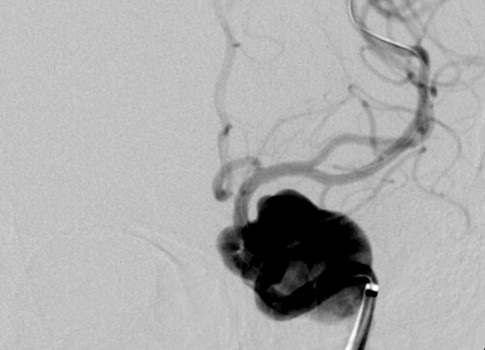

Kết quả chụp MRI, bác sĩ phát hiện bệnh nhân túi phình khổng lồ hình thoi trong động mạch não với chiều dài 40mm, đường kính 20mm. Bệnh lý túi phình thường chỉ gặp ở người lớn tuổi với túi phình chỉ khoảng 3mm đến 5mm, nhưng chị Diễm T. mới ngoài 30 tuổi đã mắc phải là trường hợp ít gặp. Mặt khác, kích thước túi phình quá lớn, nguy cơ có thể vỡ bất kỳ lúc nào sẽ khiến người bệnh bị nhồi máu não, tử vong hoặc yếu liệt cơ thể.

Cùng với chị Diễm T. bệnh viện đã thực hiện thành công phương pháp trên cho bà Nguyễn Thị S. (61 tuổi, ngụ tại Sóc Trăng). Bà S. nhập viện do đau đầu âm ỉ kéo dài, không có biểu hiện yếu liệt. Người bệnh có tiền sử bị tăng huyết áp, đái tháo đường đang trong giai đoạn điều trị. Kết quả chụp MRI cho thấy, bệnh nhân bị túi phình khổng lồ động mạch não bên trái nội sọ, kích thước 35mm.

Cả 2 trường hợp này đã được đặt stent chuyển dòng để hạn chế nguy cơ tai biến mạch máu não do túi phình gây ra về sau. Phương pháp đặt stent chuyển dòng này chỉ áp dụng khi các phương pháp khác đã thất bại do chi phí đắt và tiên lượng về lâu dài (trên 10 năm chưa được chứng minh).